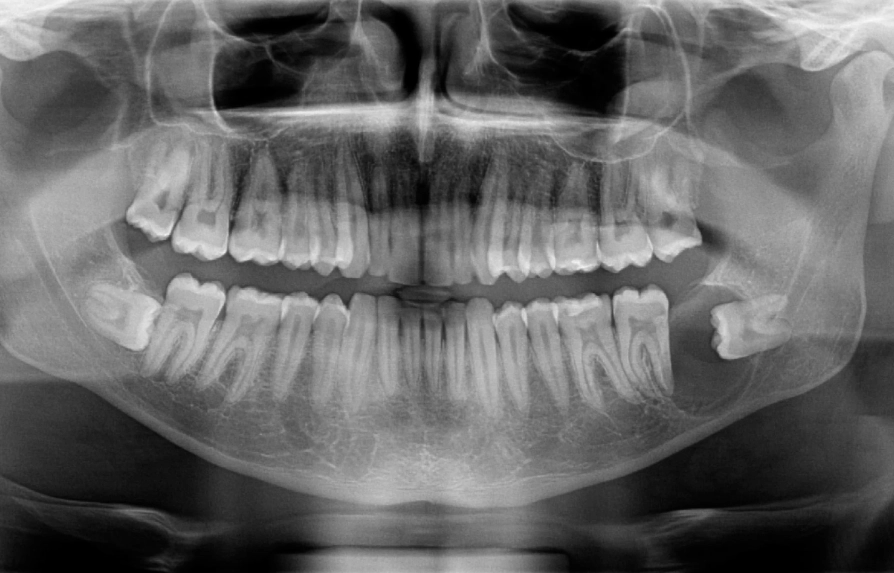

1. Panoramic X-ray (OPG): This is the first and most common step. It gives a broad view of both jaws, all teeth, and the sinuses. A cyst appears as a well-defined, dark (radiolucent) area around the crown of the impacted wisdom tooth, often with a thin white border. It looks like a dark halo.